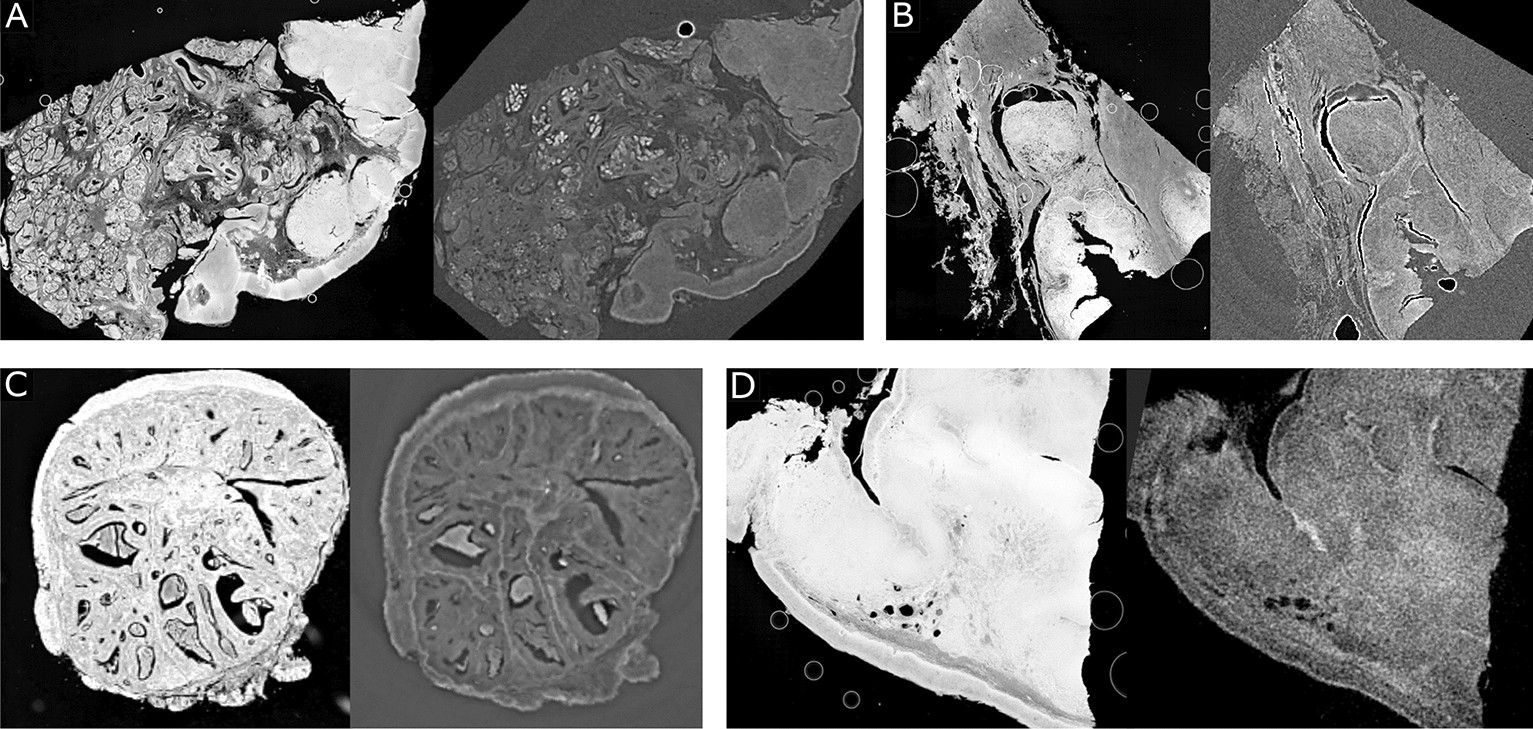

Fig. 2

Preprocessed histology slides and the registered CT slices of different tissues and imaging modalities. (A) and (B) Tonsil tissues and phase-contrast CTs. (C) Tumor tissue and phase-contrast CT. (D) Tonsil tissue and absorption CT.